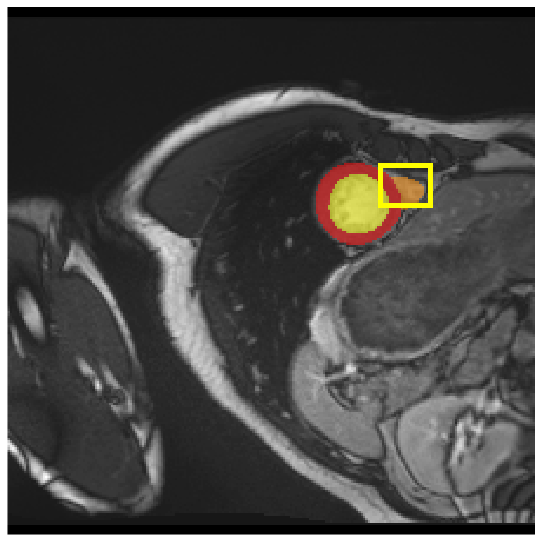

Medical image segmentation plays a critical role in various diagnostic workflows, as it enables accurate delineation of anatomical structures and pathological regions, thereby enhancing disease interpretation, treatment planning, and outcome prediction. Jang et al. [1] has demonstrated that improved segmentation performance can lead directly to reduced diagnostic error rates and increased clinician confidence. Building on the remarkable success of deep learning across diverse domains [2, 3, 4, 5], recent progress in medical image segmentation has been primarily driven by deep learning. Since the introduction of U-Net [6], segmentation methods have rapidly evolved, with convolutional neural networks (CNN)-based models [7, 8, 9] and Transformer-based models [10, 11, 12] showing superior performance in computed tomography (CT) and magnetic resonance imaging (MRI) segmentation. However, various challenges such as blurriness, noise, and low contrast often hinder the accurate diagnosis of diseases. Applying various image enhancement techniques to generate an enhanced image from the input can alleviate this problem, as existing methods have demonstrated improved segmentation accuracy [13, 14, 15]. Nevertheless, input images may unintentionally lose crucial information contained in the original image during enhancement. As a result, the segmentation model suffers from performance degradation (Fig. 1(a) and (b)). Therefore, we argue that it is crucial to leverage the advantages of both the original and enhanced images through image fusion strategies.

| (a) | (b) | (c) | (d) |

4.3.2 Visual Comparisons

Visualization of our method on the Synapse and ACDC datasets is shown in Fig. 3(a) and Fig. 3(b). For the Synapse dataset illustrated in Fig. 3(a), FCT failed to accurately segment SM and GB, while MERIT achieved precise segmentation of SM but struggled with GB. In contrast, our method achieved accurate segmentation of both SM and GB. Regarding the ACDC dataset shown in Fig. 3(b), while previous methods achieve comparable segmentation of the Myo and LV to the GT, they exhibit noticeable errors on the RV, including invasion into adjacent organs and misrecognition. On the other hand, our method accurately segments across all three structures Myo, LV, and RV, performing as precisely as the GT. We demonstrate the superiority of our method quantitatively and qualitatively.